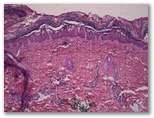

1487-R4. Paciente con las lesiones que observas en la imagen.

• Dx?

Diagnostico